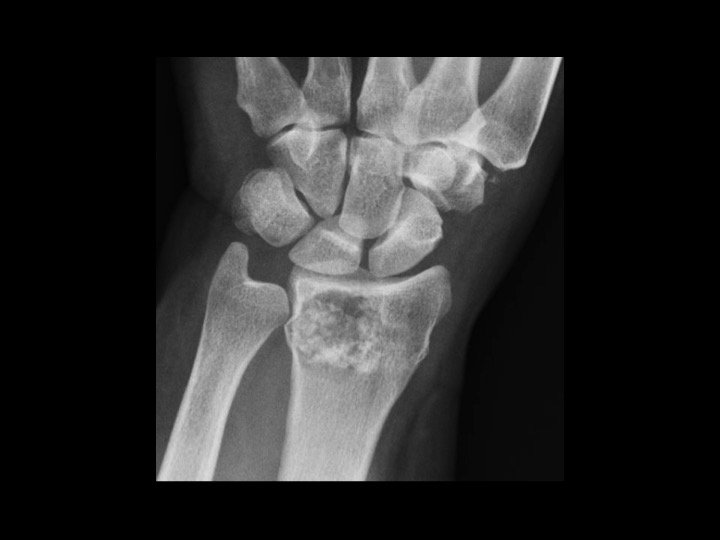

57F fell 2 weeks ago

Solitary epiphyseal enchondroma is reportedly rare (in the attached article, the incidence is 4%, higher than other series). This came to attention because of fracture after fall, though I would characterize this as a pathologic fracture, since the lesion occupies most of the DR with endosteal scalloping. In the attached article, there was no aggressive behavior on limited follow up. The radiographic appearance is non-aggressive. Is that sufficient to assume this is an epiphyseal enchondroma, not requiring close and continued imaging follow up? Or does the epiphyseal location raise suspicion and require continued surveillance after the fracture has healed? I imagine this might require currettage and grafting, at which time there would be pathology...but this is being followed currently.

enchondroma ( RID4128 )